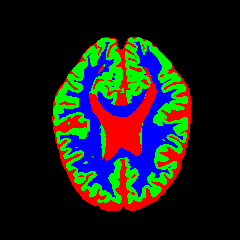

• OASIS-1 [34]: Derived from the Open Access Series of Imaging Studies, this dataset comprises T1-weighted MRI scans from 421 subjects (aged 18–96). The images were acquired with a resolution of 176×208176\times 208 pixels and a slice thickness of 1.25 mm (TR=9.79.7 ms, TE=4.04.0 ms, TI=2020 ms). Following standard protocols, we utilize the provided manual segmentation masks for Cerebrospinal Fluid (CSF), Grey Matter (GM), and White Matter (WM).

7 Qualitative Evaluation

Fig. 8 and Fig. 10 provide qualitative comparisons on the OASIS-1 and MRBrainS13 datasets, respectively. It is visually evident that the baseline predictions (c) and standard augmentations (e.g., (d), (g), (i)) frequently suffer from noisy artifacts, blurred boundaries, and mis-segmentation of intricate anatomical structures. In stark contrast, our ”Ours+” enhanced methods (e.g., (e), (h), (k)) consistently produce segmentation maps that are visibly cleaner, more spatially coherent, and demonstrate significantly sharper adherence to the Ground Truth (b). This superior fidelity is particularly noticeable in the complex sulcal patterns and holds true across all three backbones (rows), confirming that our framework yields more robust and anatomically plausible results.